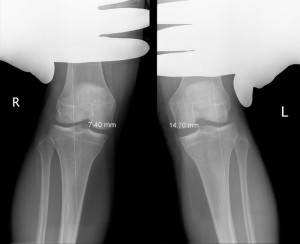

Состояние суставного хряща является важным не только для диагностики ОА, но и для оценки прогрессирования заболевания и проводимого лечения. Суммарная толщина суставного хряща на рентгенограммах определяется измерением ширины рентгеновской суставной щели между суставными поверхностями эпифизов костей. Ширина суставной щели до настоящего времени используется, как основной показатель в рентгенологической диагностике ОА, и стандартная рентгенография коленных суставов в прямой и боковой проекциях рекомендуется WHO и ILAR, как метод выбора для оценки динамики изменений в суставном хряще при проведении клинических испытаний лекарственных препаратов.

Рентгенологические симптомы, обязательные для постановки диагноза остеоартроза

Сужение рентгеновской суставной щели – один из самых важных рентгенологических симптомов, имеющий прямую коррелятивную связь с патологическими изменениями, происходящими в суставном хряще. Известно, что уменьшение в объеме суставного хряща распределяется неравномерно на разных участках суставной поверхности, в связи с чем рентгеновская суставная щель в разных отделах сустава имеет различную ширину. Согласно рекомендациям WHO/ILAR ширину рентгеновской суставной щели необходимо измерять в наиболее суженном участке. Считается, что в патологически измененном суставе именно этот участок испытывает наибольшие механические нагрузки (для коленного сустава – это медиальные отделы, для тазобедренного сустава – верхнемедиальные, реже – верхнелатеральные отделы). Анатомическими ориентирами, используемыми для измерения суставной щели на рентгенограммах крупных суставов являются:

Коленные суставы – одни из самых трудных для правильного рентгенологического исследования из–за их структурной сложности и широкого диапазона движений. ОА в коленных суставах может быть ограниченно распространенным даже в определенном отделе сустава, что также затрудняет диагностику изменений в суставе. Последние клинические и эпидемиологические работы подтвердили важность исследования пателлофеморального сустава в оценке ОА коленного сустава, так как совместное исследование этих суставов обнаруживает заболевание приблизительно в 50% от всех обследованных больных и доказывает, что к прямой рентгенографии коленных суставов необходимо в обязательном порядке добавлять прицельный снимок надколенника в боковой или аксиальной проекции. Незначительно согнутый в положении стоя и в прямой проекции коленный сустав является наиболее приемлемым положением для объективной оценки ширины суставной щели. Каждый коленный сустав сгибается так, чтобы опорные площадки суставной поверхности большеберцовой кости стали горизонтальными, шли параллельно с центральным рентгеновским пучком и были перпендикулярны кассете. Центр сустава (суставной щели) должен совпадать с центром рентгеновского луча. Рентгенологическое исследование феморопателлярного сустава может быть проведено в положении больного лежа на животе с максимально согнутой в коленном суставе ногой или с использованием метода Ahlback, когда больной стоит и коленный сустав согнут под углом 30° от вертикального положения. В этом положении сустав находится под функциональной нагрузкой, гарантируется, что поверхности сустава хорошо видны, обеспечивается более точная оценка хрящевой ткани, чем в том случае, когда больному проводится исследование в положении лежа.

Ранние рентгенологические признаки (соответствуют 1–2 стадиям артроза по Kellgren):

1. Вытягивание и заострение краев межмыщелкового возвышения большеберцовой кости (в месте прикрепления крестообразной связки).

2. Небольшое сужение суставной щели (чаще в медиальном отделе сустава).

3. Заострение краев суставных поверхностей мыщелков бедренной и большеберцовой кости, чаще в медиальном отделе сустава (связано с большей нагрузкой на этот отдел сустава), особенно при наличии варусной деформации сустава; реже – в латеральной части или одновременно в обеих половинах суставной поверхности (рис. 2).